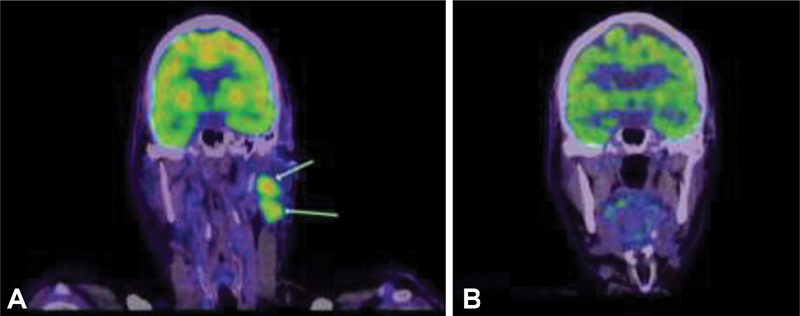

|?Fig. 1Positron emission tomography (PET) scans showing (A) 18-fluoro-2-deoxy-glucose avid left cervical lymphadenopathy at diagnosis of metastatic Merkel cell carcinoma in July 2018; (B) complete resolution of cervical lymphadenopathy in April 2019 following 5 months of treatment with second-line avelumab.

In July 2018, the patient presented with left cervical lymphadenopathy. A PET/CT scan also demonstrated multiple bony metastases and two liver metastases. A core biopsy from a cervical node confirmed metastatic MCC. Palliative carboplatin and etoposide drugs were commenced in August 2018. Follow-up imaging post three cycles of chemotherapy in October 2018 revealed a partial response. The patient was then eligible for second-line avelumab 10?mg/kg 2-weekly which he commenced in December 2018. A PET/CT scan performed 5 months later in April 2019 revealed a complete response (CR) ([Fig. 2]). By December 2020, the patient had ceased avelumab and is in complete remission (on PET/CT scanning) from MCC. For pragmatic reasons, we decided with the patient's input to watch him closely off therapy. Coming to hospital every 2 weeks for his infusion was becoming onerous. Therapy can be reinstituted if he relapses. He remains in clinical remission when seen in July 2021.